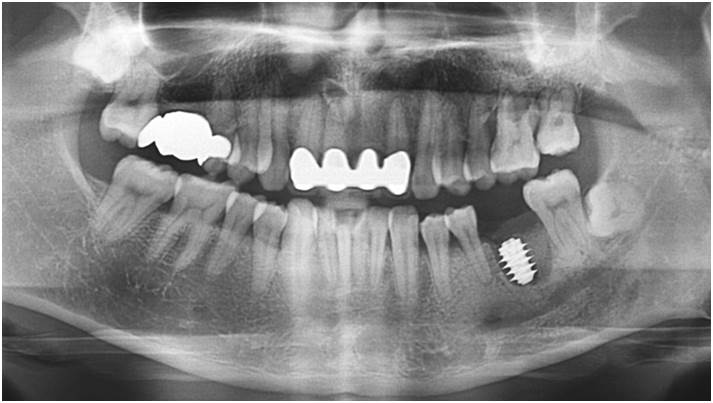

“AnyRidge with Root Membrane Technique shows

comparable long-term success rates to

conventional immediate implants. ”

Clinical case: Replacement of fractured central incisor (#11) with immediate implant

& Root Membrane Technique

- Courtesy of Dr. Miltiadis Mitsias, Greece -

Keywords

AnyRidge, Root Membrane Technique, retrospective study, long-term study, immediate implants, bone resorption, bone preservation, Dr. Miltiadis Mitsias,survival, success, maxillary anterior, single replacement

Products:

AnyRidge implant system, Root Membrane kit

Reference

The Root Membrane Technique: A retrospective clinical study with up to 10 years of follow-up./Implant Dent. 2018 Oct;27(5):564-574

https://www.ncbi.nlm.nih.gov/pubmed/30161062